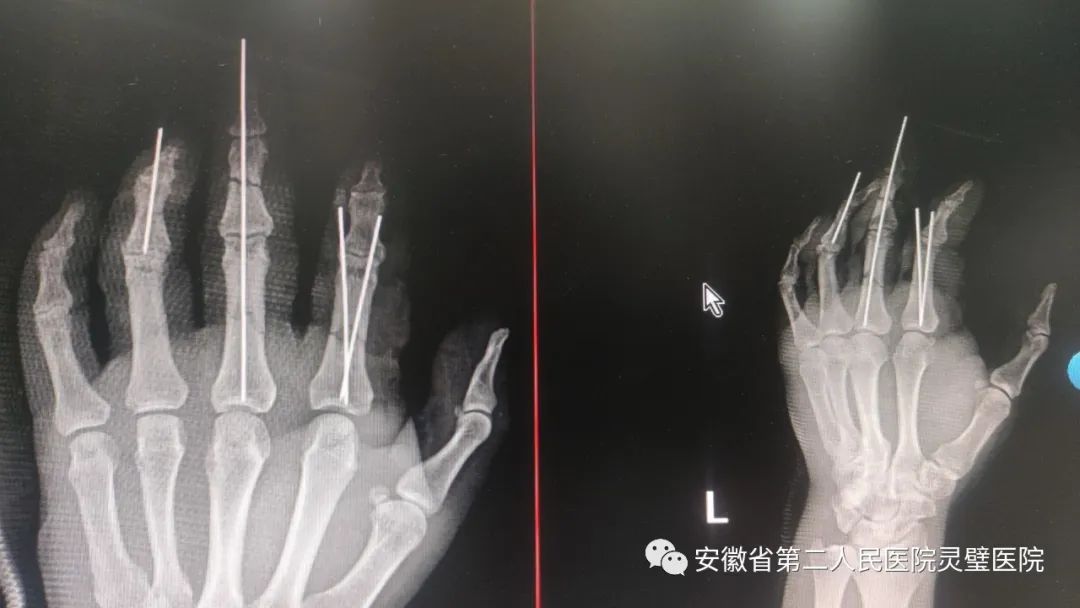

机器绞伤致左手开放性损伤伴骨折

患者男,42岁。入院前不慎被机器绞伤左手,左手食指掌指关节掌侧组织不规则撕裂,桡侧指固有动脉及伴行静脉不同程度挫伤,同侧指神经牵拉伤,近节指骨骨折、断端分离。左手中指尺侧指固有动脉牵拉、挫裂伤,静脉断裂,暴露见中节及近节指骨骨折断端明显骨折,成角畸形。急诊手足外科团队迅速开通手术绿色通道,为该患者实施多发指骨骨折切开复位内固定术+皮瓣清创成型术,术后透视见2-4指指骨断端对位良好,术中少量出血,患者安返病房。